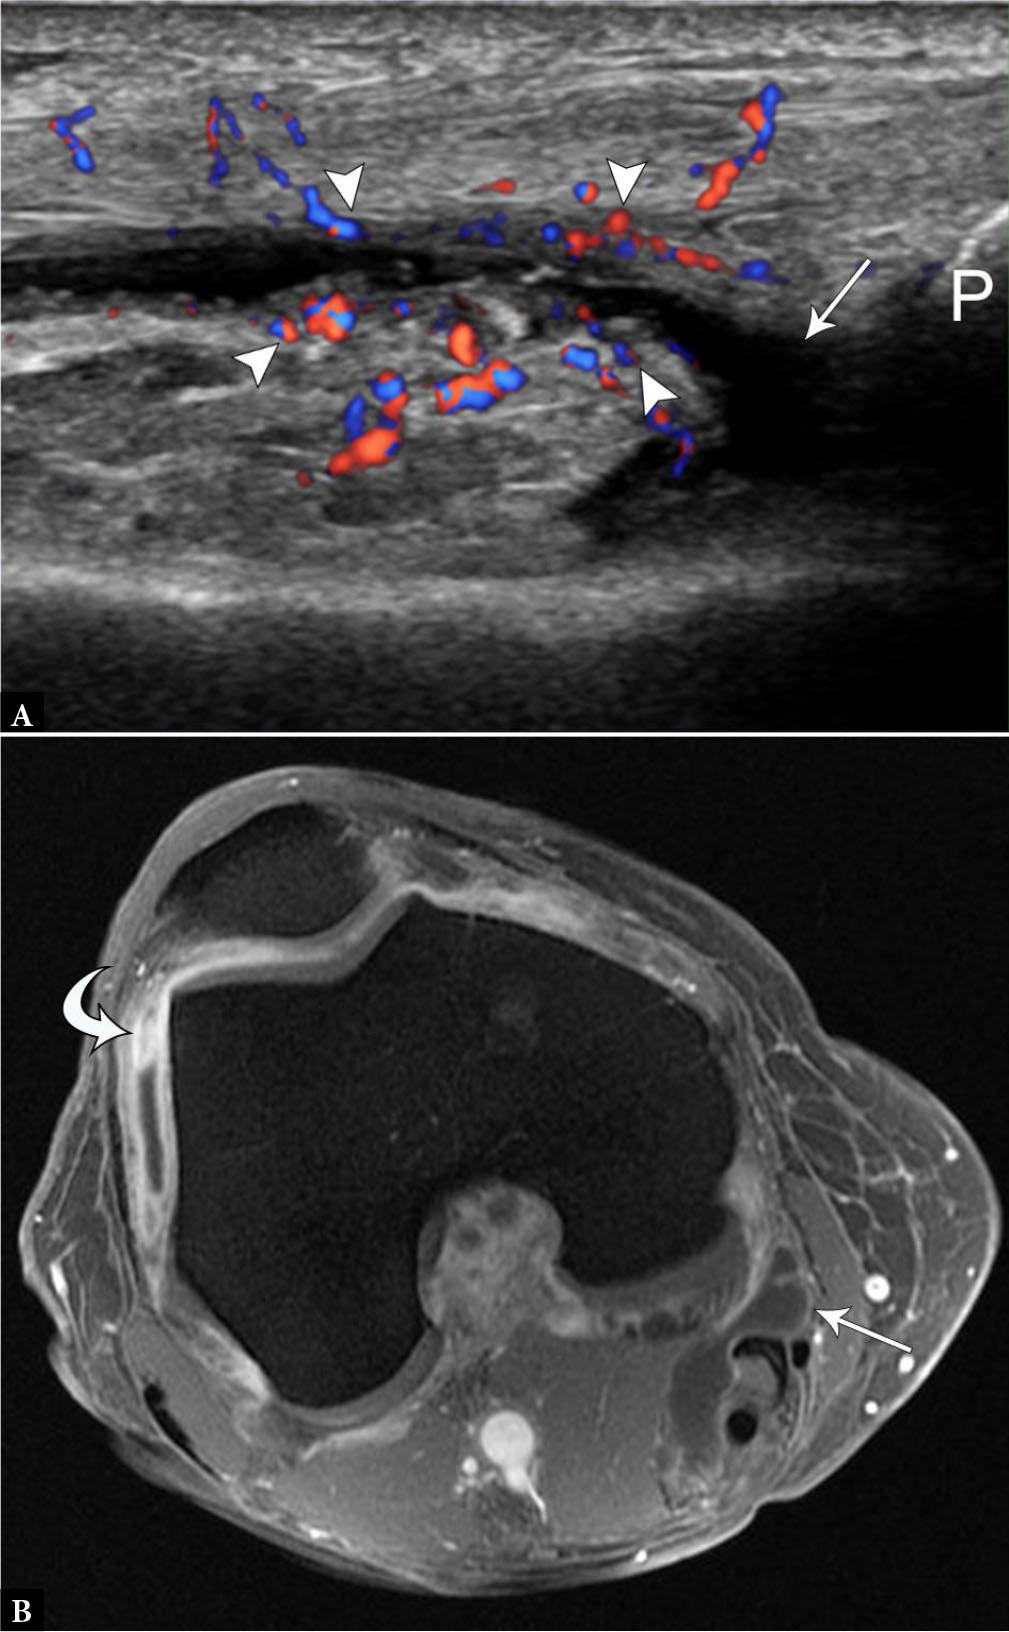

Fig. 2.

57-year-old female with osteoarthritis and synovitis. A. Longitudinal color Doppler US image superior to the patella (P) demonstrates small suprapatellar joint effusion (arrow) with hyperemic, thickened peripheral synovium (arrowheads). B. Post-contrast axial spoiled gradient echo MR image of the knee shows thickened and enhancing synovium, most prominent in the lateral gutter (curved arrow), compared to normal synovial enhancement of a Baker’s cyst (arrow). P – patella